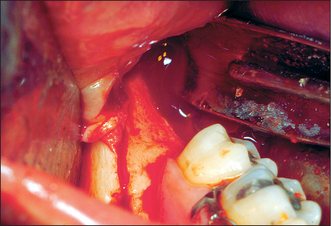

4. The patient in Fig. 12.19 presents with a pronounced labial fraenum and a median diastema.

(a) How else might the extent of the fraenum be visualized?

(b) What are the indications for lingual fraenectomy?

image

Fig. 12.19 See question 4.